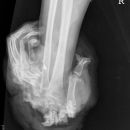

Amputation Hand